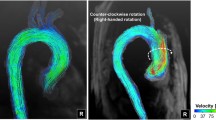

To test the hypothesis that the spiral flow pattern in the human aorta may play a beneficial role in the transport of oxygen, hence sparing the ascending aorta from atherosclerosis, a comparative study on the distribution of oxygen flux to the arterial wall was carried out numerically for three aorta models. The first one (Model 1) was constructed based on MRI images of a human aorta acquired in vivo. The second (Model 2) was made the same as Model 1 but without the three branches. The third (Model 3) was similar to Model 2 only with the aortic torsion removed. The results showed that without the torsion, the flow fashion in Model 3 was very different from the swirling flows in Models 1 and 2 and exhibited the typical characteristics of Dean flow with two symmetrical helical structures. In Models 1 and 2, the average Sherwood number (Sh) in the ascending aorta with the presence of a strong spiral flow was not only higher than that in the inner wall of the descending aorta where the spiral flow faded out, but also generally higher than that in Model 3. The comparison between Models 2 and 3 demonstrated that the averaged Sh from ascending aorta to aortic arch was relatively higher for Model 2. In conclusion, the spiral or swirling flow may have certain physiological significance in the aorta and play a positive role in the transport of oxygen by enhancing oxygen flux to the arterial wall.